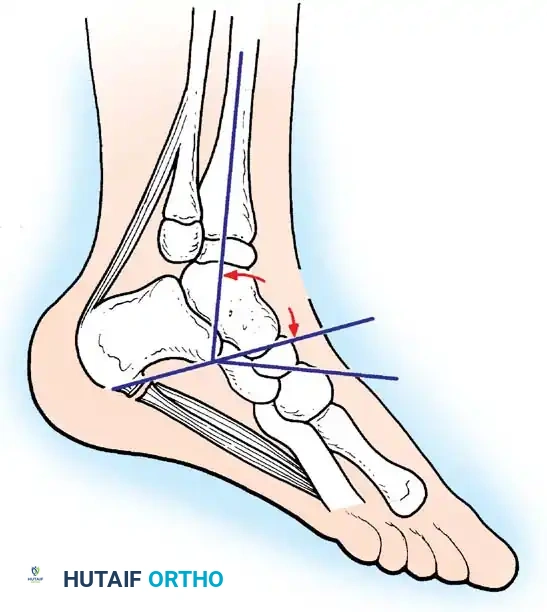

The foot and ankle are the most common sites of paralytic deformity. Imbalances between the dorsiflexors, plantarflexors, invertors, and evertors rapidly lead to complex, multiplanar deformities.

Image

Paralytic Equinus:

Caused by paralysis of the anterior tibial muscles with sparing of the triceps surae. If dynamic, it is managed with a posterior tibial tendon transfer through the interosseous membrane to the dorsum of the foot.